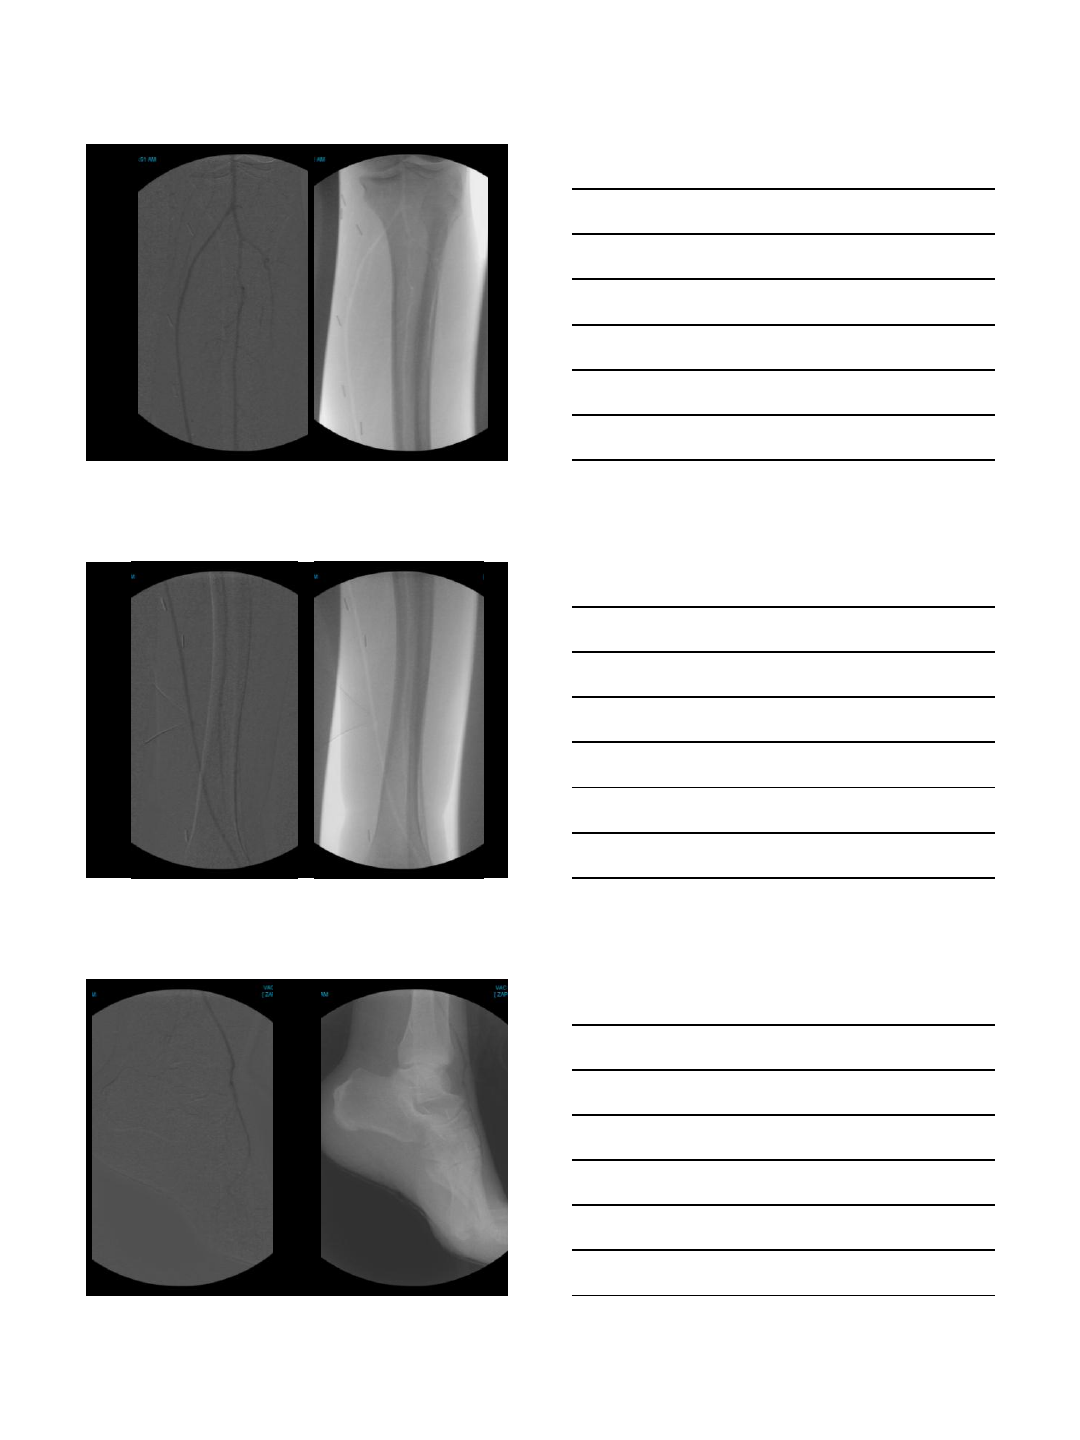

Carbon Dioxide Imaging

Lower Extremity

Carbon Dioxide Lower Extremity

Angiography

Carbon Dioxide performs well in

occlusive disease

Peripheral Interventions

SFA Occlusion

Post Angioplasty and

Atherectomy